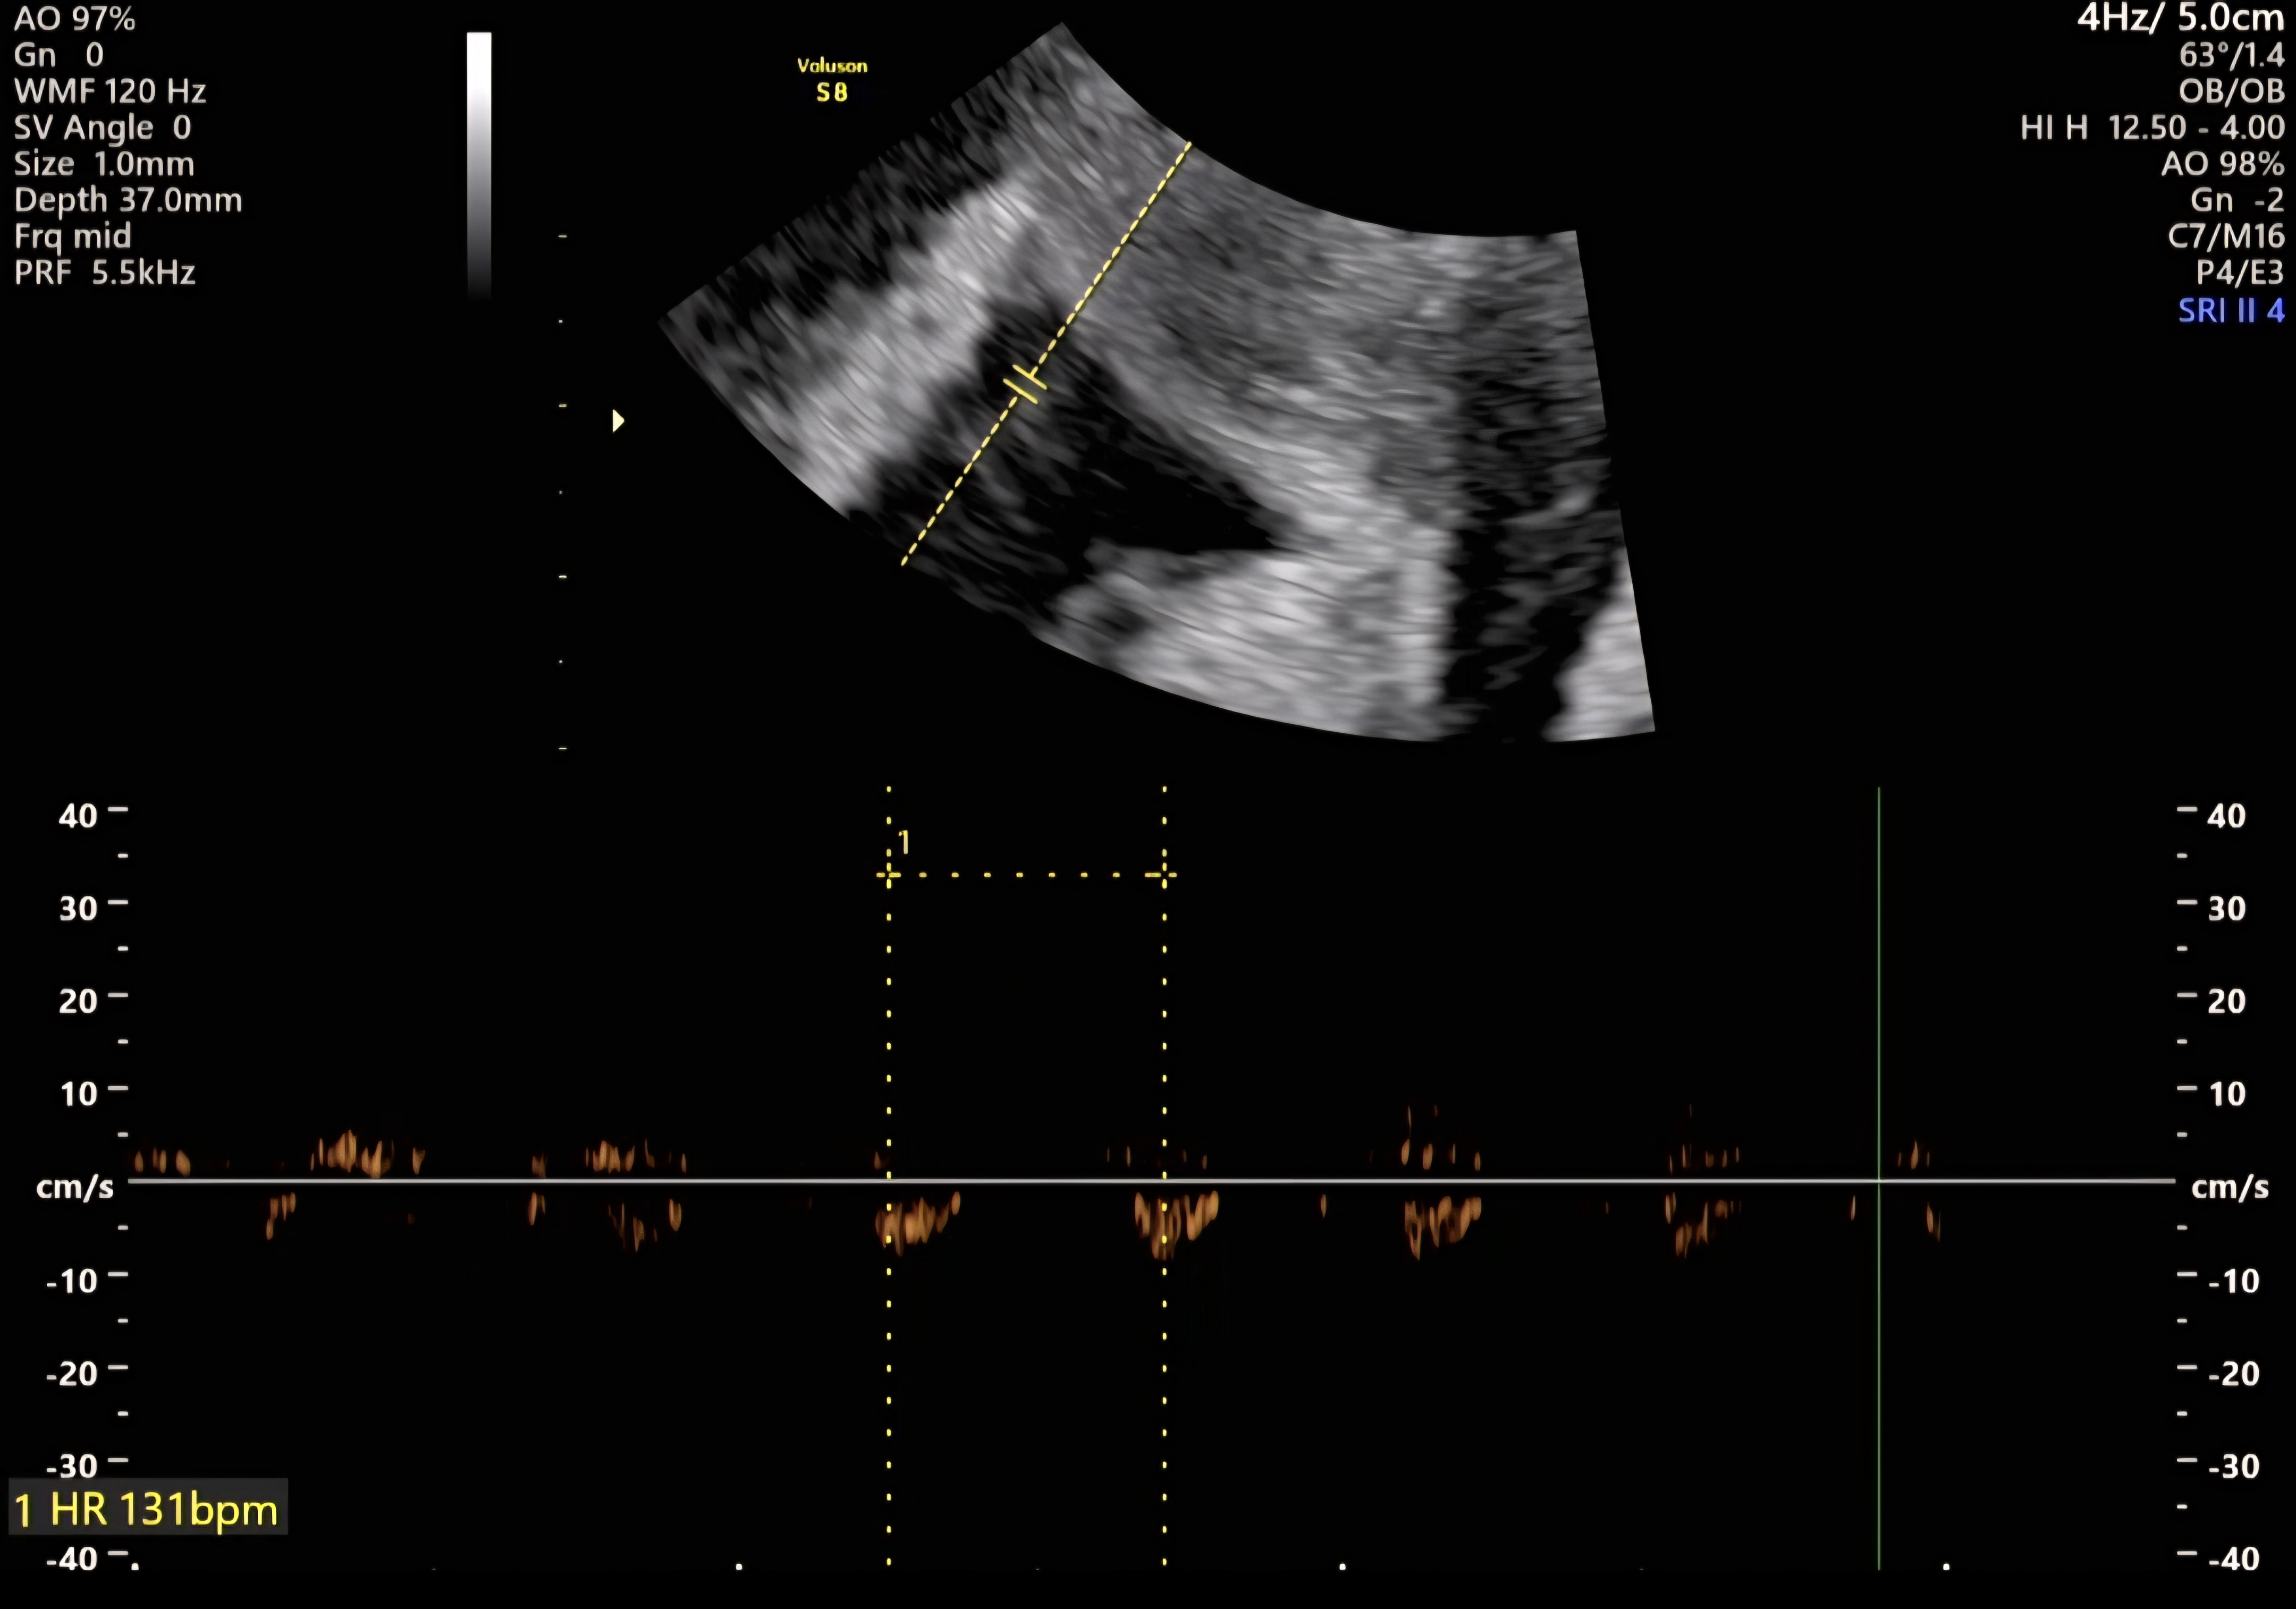

| 치료 도중 느꼈던 가장 기뻤던 순간과 절망적인 것들은 무엇인가요? 잊지 못할 경험이 있나요? | 가장 기뻤던 순간은 아기의 심장소리를 들었을 때였고, 가장 힘들었던 순간은 이식을 하고 싶었지만 간 수치 문제로 치료를 잠시 멈춰야 했을 때였습니다. |